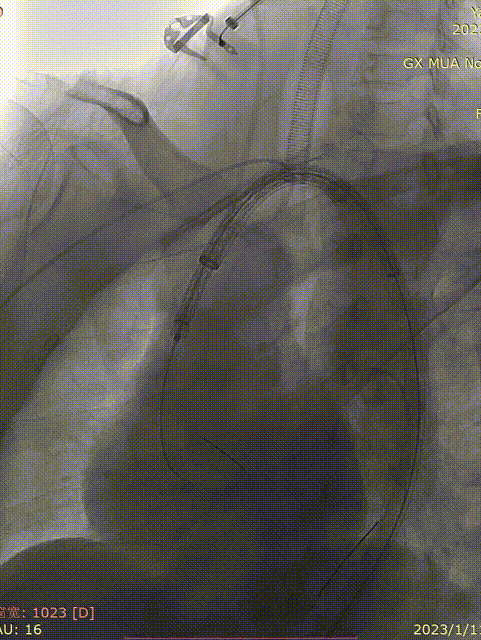

远端接主体

第一支架释放完毕后造影可见:LCCA显影良好,支架近端完全贴壁无鸟嘴。

远端LSA显影和Ib型漏,故在在第一支架内接入同型号第二支架,内漏消失,LSA显影延迟。

gore医疗怎么样「胸有乾坤」化险为夷,通险畅机——GORE® TAG® 胸主动脉覆膜支架治疗累及异形弓部动脉瘤_https://www.jmylbn.com_新闻资讯_第22张

第一支架远端存在Ib型漏

gore医疗怎么样「胸有乾坤」化险为夷,通险畅机——GORE® TAG® 胸主动脉覆膜支架治疗累及异形弓部动脉瘤_https://www.jmylbn.com_新闻资讯_第23张

补充第二支架

gore医疗怎么样「胸有乾坤」化险为夷,通险畅机——GORE® TAG® 胸主动脉覆膜支架治疗累及异形弓部动脉瘤_https://www.jmylbn.com_新闻资讯_第24张

最终造影

术后复查

复查造影可见胸主动脉显影良好,支架在位无鸟嘴,支架内显影良好无内漏,瘤腔造影剂无明显外溢,右头臂动脉,左颈总动脉显影良好,患者声嘶症状即刻减轻,但仍能触及颈部包块轻微搏动,考虑为LSA返流所致。